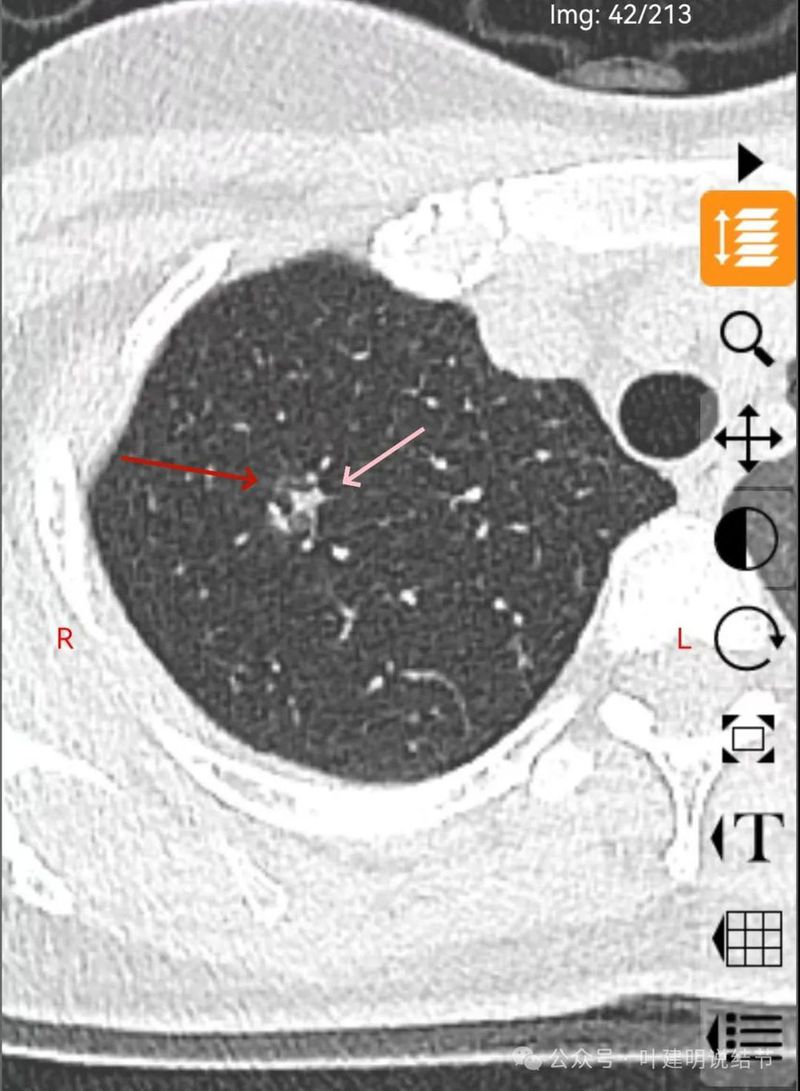

磨玻璃密度伴灶内支气管扩张。

支气管扩张,病灶磨玻璃密度,有血管进入穿行。

边缘处密度较淡。